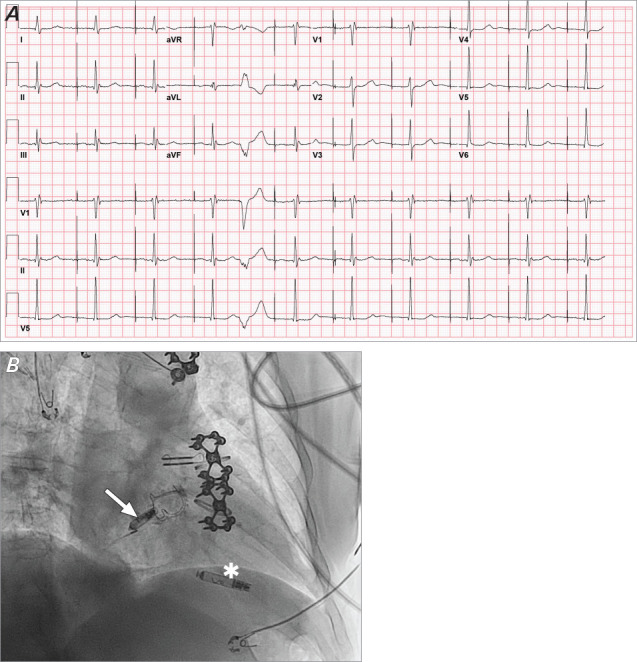

The AVEIR DR (Abbott Medical) was the first dual-chamber leadless pacing system approved by the US Food and Drug Administration. Many patients with sinus node dysfunction have physiologically normal atrioventricular conduction, so an atrial-only pacing system may be appropriate for them. Three patients with symptomatic sinus node dysfunction underwent device implantation with electrophysiologic study, including incremental atrial pacing until loss of 1:1 atrioventricular conduction (atrioventricular Wenckebach cycle length) and His-ventricular interval measurement. If the atrioventricular Wenckebach cycle length was no more than 400 milliseconds and the His-ventricular interval measurement was no more than 55 milliseconds, single-chamber atrial implantation was deemed appropriate. Each patient displayed a different response to atrioventricular conduction testing, demonstrating how electrophysiologic study before device implantation may identify patients for whom atrial-only pacing is not appropriate.